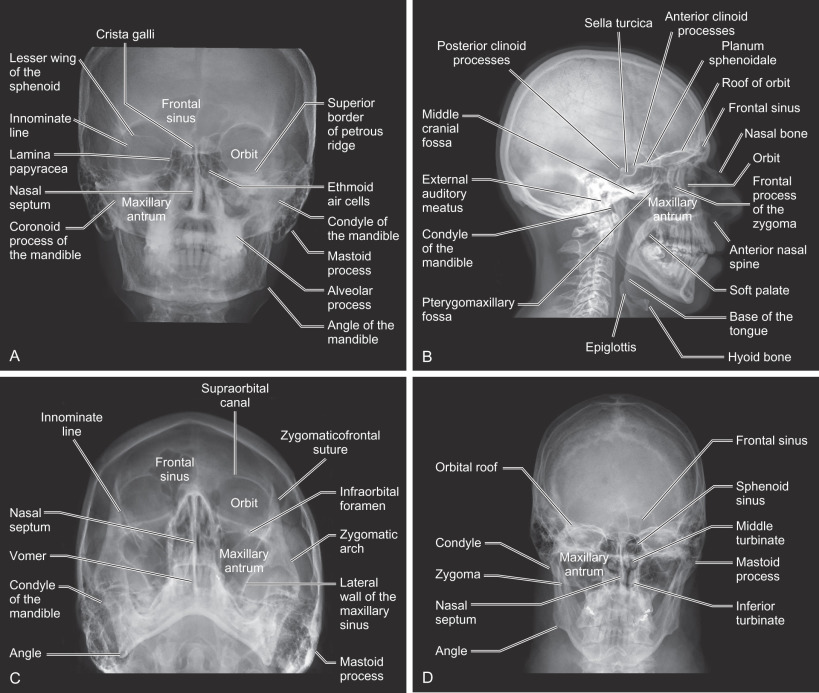

The surgical anatomy is shown in Figs. 1.2.1–1.2.10 :

Plain radiography: Figs. 1.2.1 – 1.2.2

Radiographs of the skull at various angles allow visualization of the major osseous structures of the face and mandible. Plain radiographs are named based on the projection of the X-ray beam. The most common radiographs of the face in the trauma setting include: standard occipitomental (30 degrees OM or Waters view), posteroanterior (PA skull or Towne view), reverse Towne’s and the true lateral skull ( Fig. 1.2.1 ). The submentovertex view, which requires hyperextension of the neck, is not obtained given the risk of a concomitant cervical spine injury seen in 2.2% of patients with maxillofacial fractures. Each projection of the face best demonstrates certain osseous features of the craniofacial skeleton ( Table 1.2.1 ). However, overlapping osseous structures limit evaluation of the entire craniofacial skeleton, especially the midface, sinuses, and skull base. Moreover, the patient must be able to cooperate with positioning to obtain the various projections. This is impossible with patients suffering from traumatic brain injuries associated with craniofacial fractures.